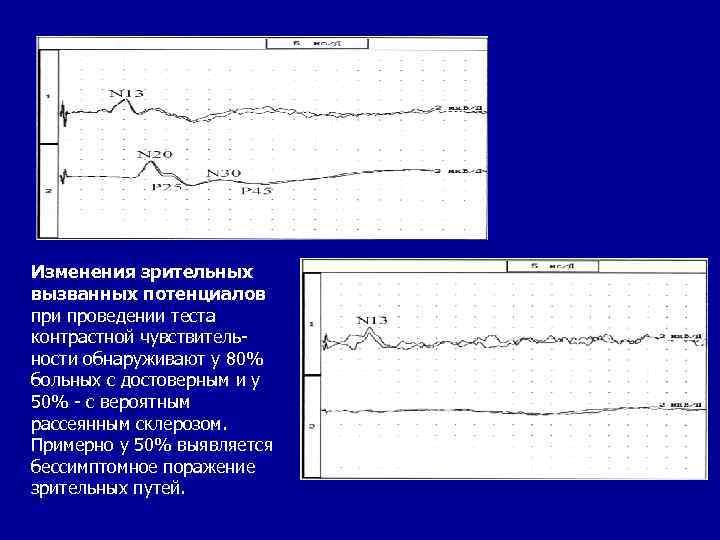

ИНСТРУМЕНТАЛЬНЫЕ МЕТОДЫ ИССЛЕДОВАНИЯ • Целесообразность исследования вызванных потенциалов у больных PC состоит в обнаружении очагов поражения ЦНС, которые не проявляют себя клинически. Изменения характеристик кривых вызванных потенциалов - неспецифичный для PC тест, характеризует замедление проведения импульса по определенным системам. Изменения зрительных вызванных потенциалов обнаруживают примерно у 80% больных; изменения слуховых вызванных потенциалов — у 50%; изменения соматосенсорных вызванных потенциалов - у 70%.

Изменения зрительных вызванных потенциалов при проведении теста контрастной чувствительности обнаруживают у 80% больных с достоверным и у 50% - с вероятным рассеянным склерозом. Примерно у 50% выявляется бессимптомное поражение зрительных путей.